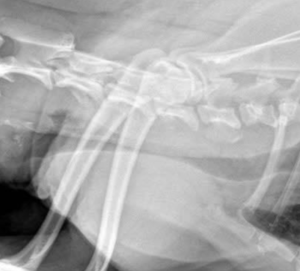

4 気管虚脱の診断

レントゲン検査(X線撮影)を行うことが重要です。犬の咳の原因には、慢性気管支炎、僧帽弁閉鎖不全症に伴う左心房拡大による気管支圧迫、肺炎など多数の可能性があり、レントゲンはそれらの病気を除外する補助的な情報を与えてくれます。

気管虚脱が疑われる場合は、吸気時と呼気時それぞれで頸部と胸部を撮影して評価します。頸部の虚脱は吸気時に、胸郭内の虚脱は呼気時に最もはっきり現れます。

レントゲン検査

胸郭外気管(胸の外):吸気時に虚脱し、呼気時に拡張する傾向があります。

胸郭内気管(胸の中):呼気時に虚脱し、吸気時に拡張する傾向があります。